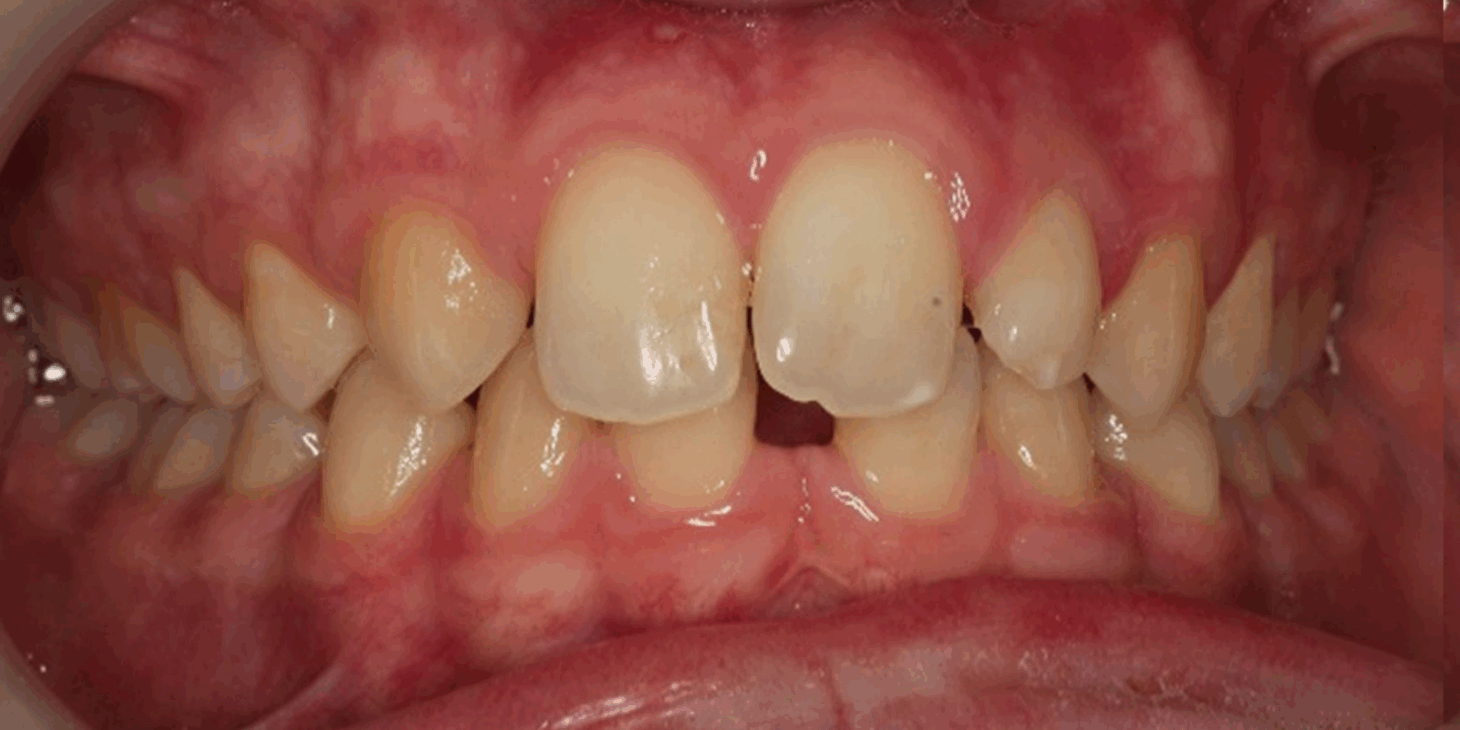

Skeletal Class II due to mandibular retrognathia, proclination of maxillary incisors, narrow arch creating a V-shaped arch, agenesis of 12, 31, 41, hyperdivergent facial pattern, moderate deep bite (2 mm), increased overjet (9 mm), asymmetric canine and molar Class II due to mandibular deviation to the left, maxillary midline deviation related to agenesis of 12, distal rotation of 35 and 45, and pronounced lower curve of Spee.

Labial incompetence, mouth breathing, tongue dysfunction